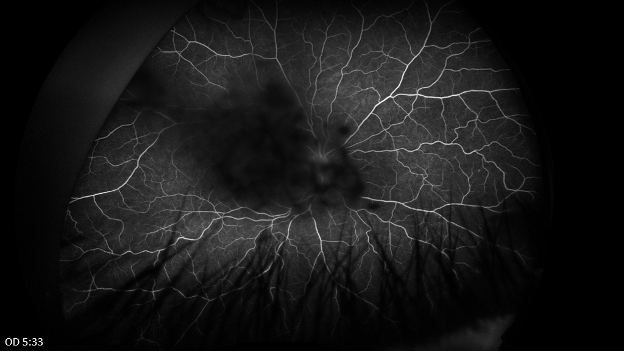

Late phase fluorescein angiography of both eyes shows central blockage in both eyes from lenticular and vitreous opacities. In the left eye there is possible leakage from the optic disc and late venous leakage inferiorly.